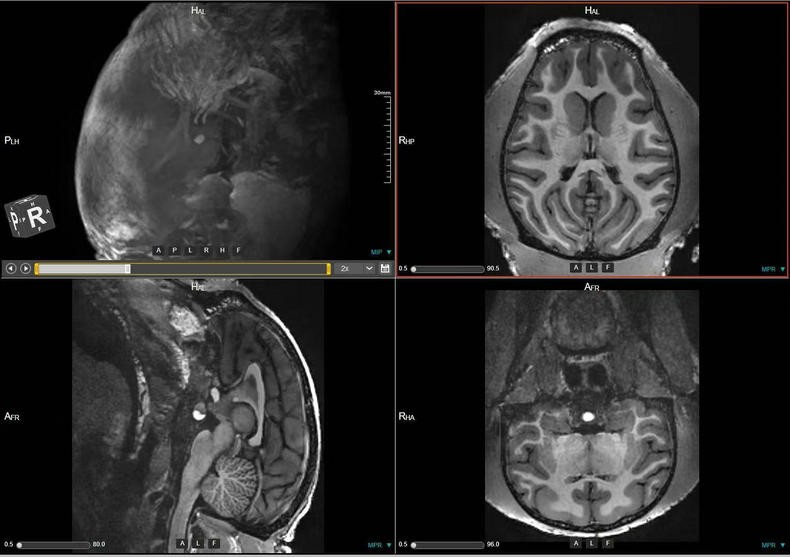

本数据集为2023-2025年对91只13-19岁中年健康雌性猕猴的脑部磁共振扫描收集的数据,主要包括T1w序列和T2w序列影像(3D影像),对于神经学、心理学、行为学等多个相关学科的研究提供丰富的脑数据支撑。

a.物种:猕猴

样本数量:91只

年龄分布:13-19岁

重量分布:4-16kg

性别分布:雌性91只

c.扫描仪规格

扫描仪类型:联影uMRNX 3.0T磁共振扫描仪器

线圈:12通道猕猴专用头线圈

d.扫描程序

麻醉程序:阿托品(0.5mg/ml)-氯胺酮(0.05mg/ml)-丙泊酚(2mg/ml),阿托品和氯胺酮之间间5-10分钟,氯胺酮和丙泊酚之间间隔5-10分钟。

麻醉和扫描间隔时间:从阿托品算起,大约25分钟,从氯胺酮算起大约15分钟。

扫描体位:仰卧头先进